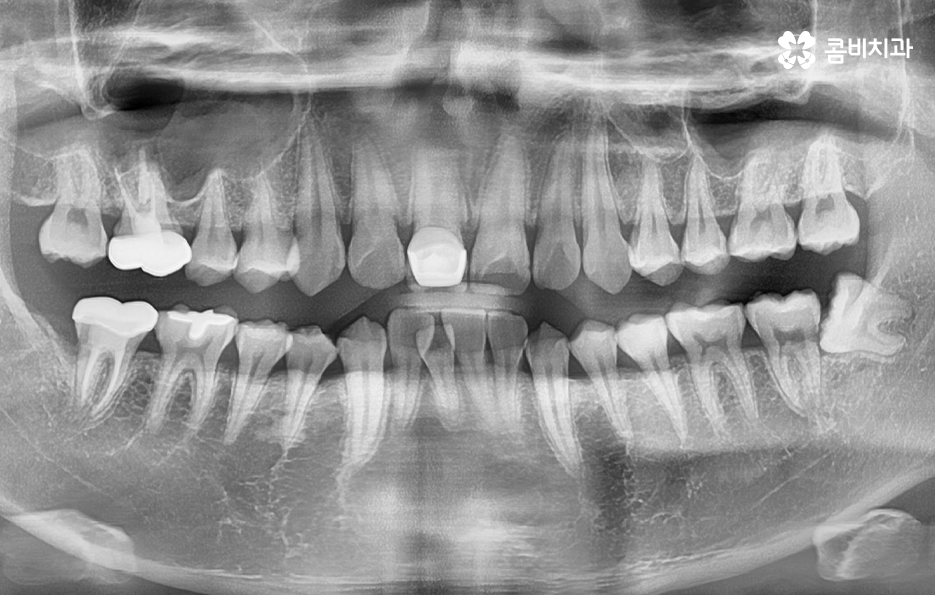

하지만 위에 보시는 환자분의 사례는 윗니와 아랫니의 교합을 고려하고 얼굴형, 골격 등을 고려했을 때도 아랫니만 교정이 가능했던 사례인데 일반적으로 윗니가 아랫니를 살짝 덮고 있어야 하는데 아랫니의 앞니 부분이 유독 안으로 들어와 있었기 때문에 아랫니교정 만으로도 치아교정이 가능했던 사례라고 보시면 좋을 거예요

치아교정 계획은 기본적으로 치열과 교합, 골격과 얼굴형을 종합적으로 따져보고 치아교정 후의 변화 결과를 미리 잘 예측하여 치료 계획이 세워지고 있는데요

위 환자분의 사례로 보면 아랫니 중에 하나가 유독 앞으로 튀어나와 있고 나머지 치아는 안으로 들어가 있기 때문에 교합으로 따져볼 때는 아랫니를 전체적으로 앞으로 이동시켜야 했기 때문에 비발치로도 충분히 교정이 가능했고 아랫니교정 만으로도 치료가 가능했어요